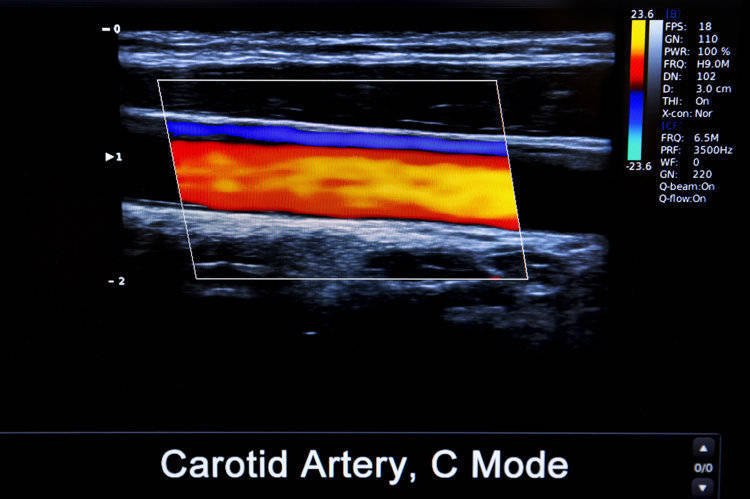

虽然全身的动脉血管都可能长出斑块,但从危害性来说,颈动脉斑块的风险更大。颈动脉斑块的形成往往预示着严重心脑血管疾病风险,权威期刊《柳叶刀》子刊曾发布过相关研究,其中统计的数据显示,仅2020年我国就有近20亿人颈动脉粥样硬化确诊患者,而且主要集中在40岁-60岁及以上人群中,其中60岁以上群体检出率几乎达到100%!